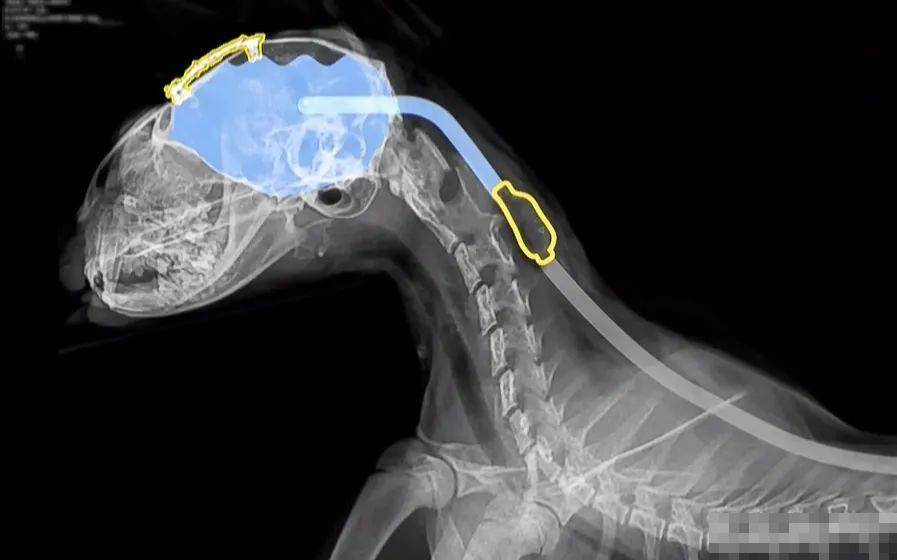

醫生需要在豆包的頭部戳一個洞,并確保有足夠的空間安裝管子,隨后將[插·入]一根水管并將其連接到泵上,再將管子的另一端[插·入]胃中,當大腦中的積液溢出而導致腦壓升高時,該設備就會自動將液體輸送到胃里,手術的過程十分漫長,小貓的主人只能焦急的等待,不久后貓咪頭部的腫塊被切除了,從醫生的表情可以看出手術進行的很成功,醫生表示只要撐過頭三天貓咪即將迎來重生。